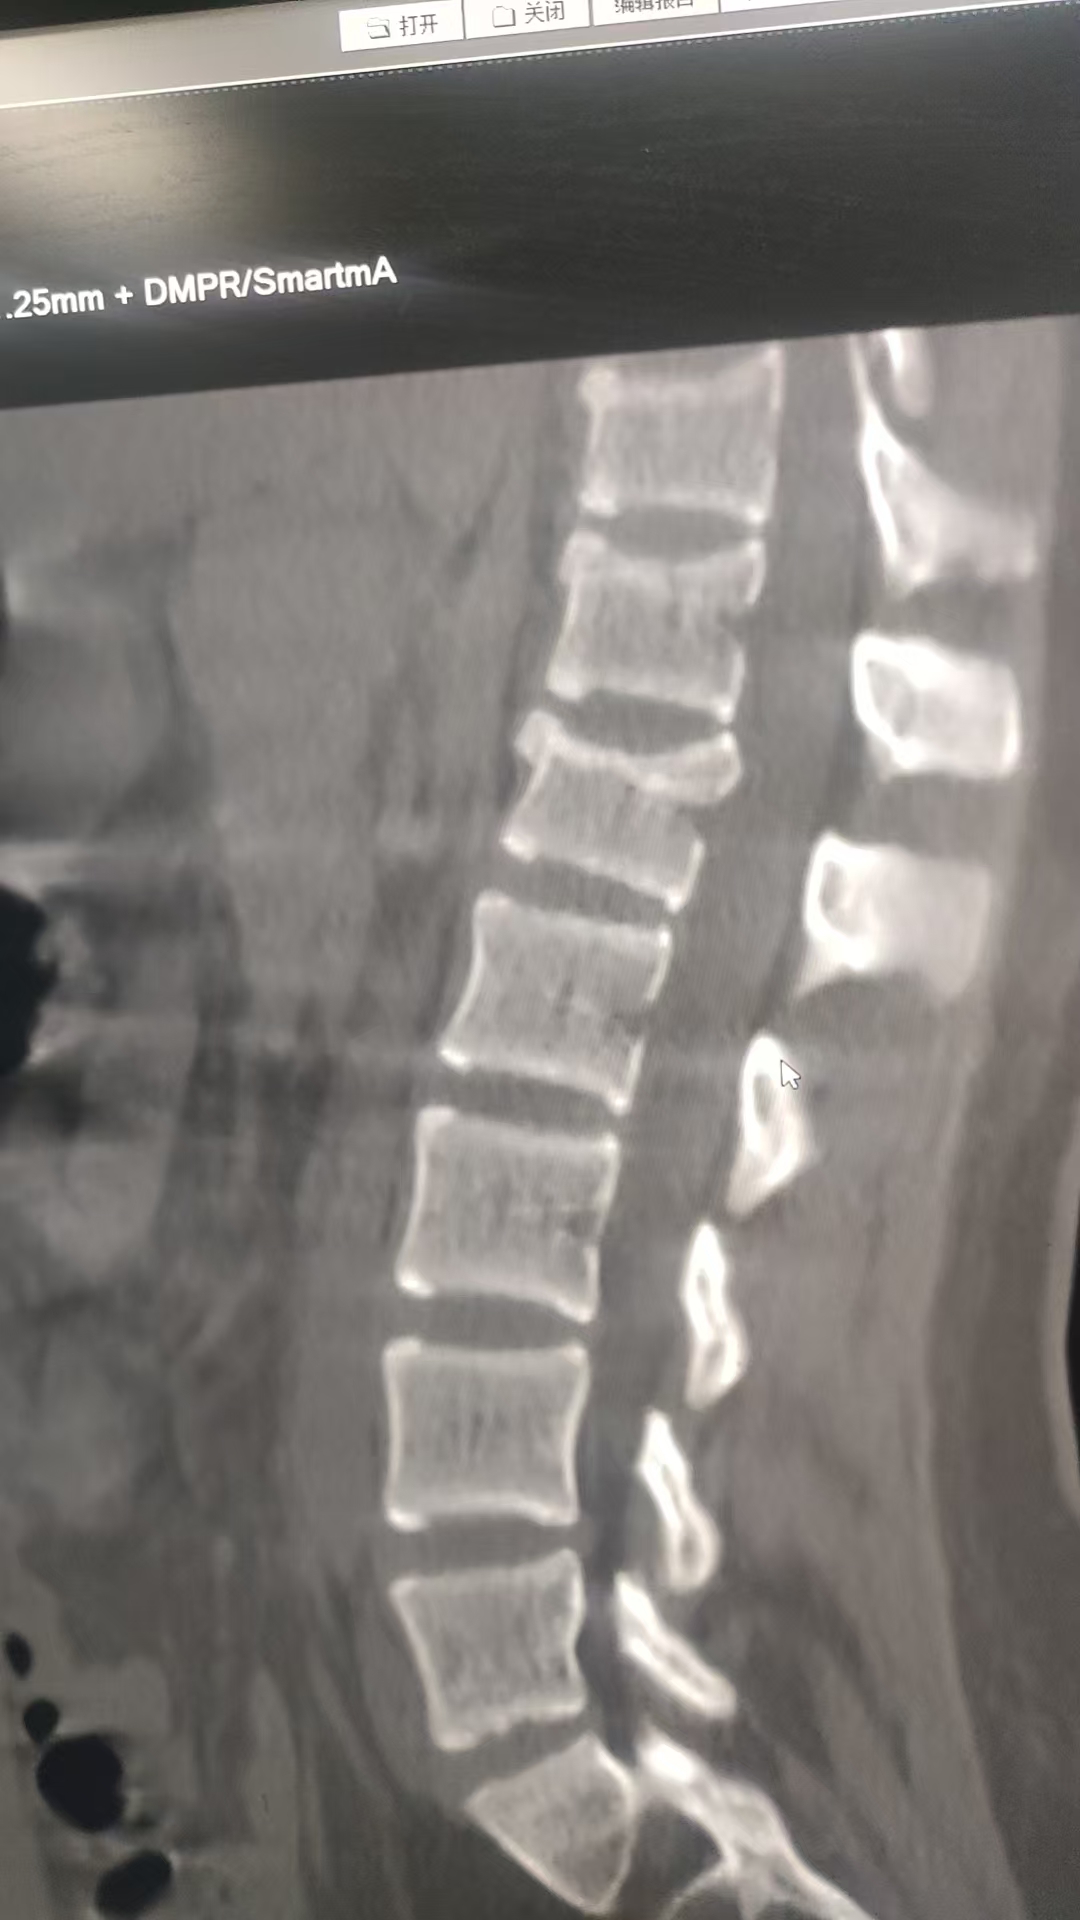

我妈是环卫工,去年七月份,,去上班开着环卫电三轮路上与一个骑电动自行车女学生相撞,我妈在机动车道正常行驶,在自行车道行驶的女学生看到前面有施工围挡,就从小路口拐到机动车道,这时与我妈的电三轮相撞,我妈说女学生骑的比较快,她的电动车从侧后面撞击了我妈的三轮车,女学生倒地受伤。一个星期后,到交警队定则,看了录像,是学生直接撞击的我妈三轮侧面。定的我妈次要责任,女孩主要责任,理由是我妈的电动三轮未在非机动车道行驶,就算是机动车,也没有驾照。 交警定的合理吗? 现在女孩定了居然定了伤残九级,起诉了我妈。 交警这责任划分 还能翻案吗? 另外请有经验的老师 看看,女孩的医生诊断是腰椎1压缩性骨折 胸椎10~12轻度压缩性骨折,应该都没到1/3。能评到十级伤残吗?

• 根据《人体损伤致残程度分级》标准:十级伤残:一椎体压缩性骨折(压缩程度达1/3),或一椎体粉碎性骨折。 ​九级伤残:二椎体压缩性骨折,或一椎体粉碎性骨折伴椎管内骨性占位等。 你描述的伤情是“腰椎1压缩性骨折、胸椎10~12轻度压缩性骨折,压缩都不到1/3”: 如果每一节椎体压缩均未达到1/3,且无粉碎性骨折或手术治疗,通常不构成九级伤残,甚至可能不构成十级伤残。 ​如果存在手术治疗、粉碎性骨折或其他并发症,则可能影响最终评定。 建议你方在诉讼中申请重新鉴定,由法院委托有资质的机构重新评估伤残等级。

• 1. 责任划分合理性: 交警定责合理——电三轮属非机动车,应走非机动车道;无驾照也属违规,所以你妈负次要责任。若不服,需在收到责任认定书3日内申请复核,但翻案概率低(有录像证明学生撞击,但你妈有车道/驾照违规)。 2. 伤残等级问题: 骨折压缩未到1/3,通常评不上九级,大概率也达不到十级(十级一般要求压缩≥1/3)。可向法院申请重新鉴定,以新结果为准。 核心:责任划分难推翻,伤残等级可申请重新鉴定,未达1/3难评上伤残。

女孩有腰椎1 和 胸椎至少3个节段的压缩性骨折。根据标准,二椎体压缩性骨折即可构成九级伤残。女孩的骨折数量远超这个标准,因此被评定为九级伤残是有依据的,甚至可能构成更高等级(如八级),具体要看压缩程度和功能受限情况。

• 一、关于交警定责是否合理 1. 定责依据: - 对方(女学生):违反《道路交通安全法》(未确保安全通行),且从非机动车道突然拐入机动车道,是事故主要诱因。 - 你母亲:电动三轮车未在非机动车道行驶,且无相应驾驶证,存在过错。 - 交警据此认定女学生主要责任、你母亲次要责任,在法律上具有合理性。 2. 复核空间: - 若对责任认定有异议,可在收到认定书之日起3日内向上一级交管部门申请复核。 - 复核重点可放在:电动三轮车的属性认定、你母亲作为环卫工在作业时的通行特殊性、对方突然变道的危险性等。 二、关于伤残等级是否过高 1. 鉴定依据: - 鉴定机构依据《人体损伤致残程度分级》5.9.6.2条“二椎体压缩性骨折”,结合女孩腰1、胸10-12椎体压缩性骨折的伤情,评定为九级伤残,符合标准。 - 即使单椎体压缩未达1/3,多椎体同时骨折的伤情已满足九级伤残的评定条件。 2. 重新鉴定建议: - 若对鉴定结论有异议,可在诉讼中向法院申请重新鉴定。 - 需提供充分证据,证明鉴定机构在伤情认定或适用标准上存在错误。 三、诉讼应对策略 1. 追加被告: - 你母亲是在执行工作任务时发生事故,可申请追加其用人单位(环卫公司)为共同被告,由公司在交强险外按责任比例承担赔偿责任。 2. 保险理赔: - 若电动三轮车投保了保险,应及时通知保险公司,由其在保险限额内承担赔偿责任。 3. 证据准备: - 收集事故现场照片、视频、证人证言,证明对方突然变道的事实。 - 准备你母亲的工作证明、工资流水,用于证明其行为属于职务行为。

• 虽然不能复核,但在法院审理时,您可以向法官提出对责任划分的异议,并提交证据(如现场录像)。法官会审查认定书作为证据的效力,如果确有错误,法院可以不采信该认定书,重新划分赔偿比例。从您描述的“压缩不到1/3”来看,评九级确实偏高了,评十级的可能性更大。